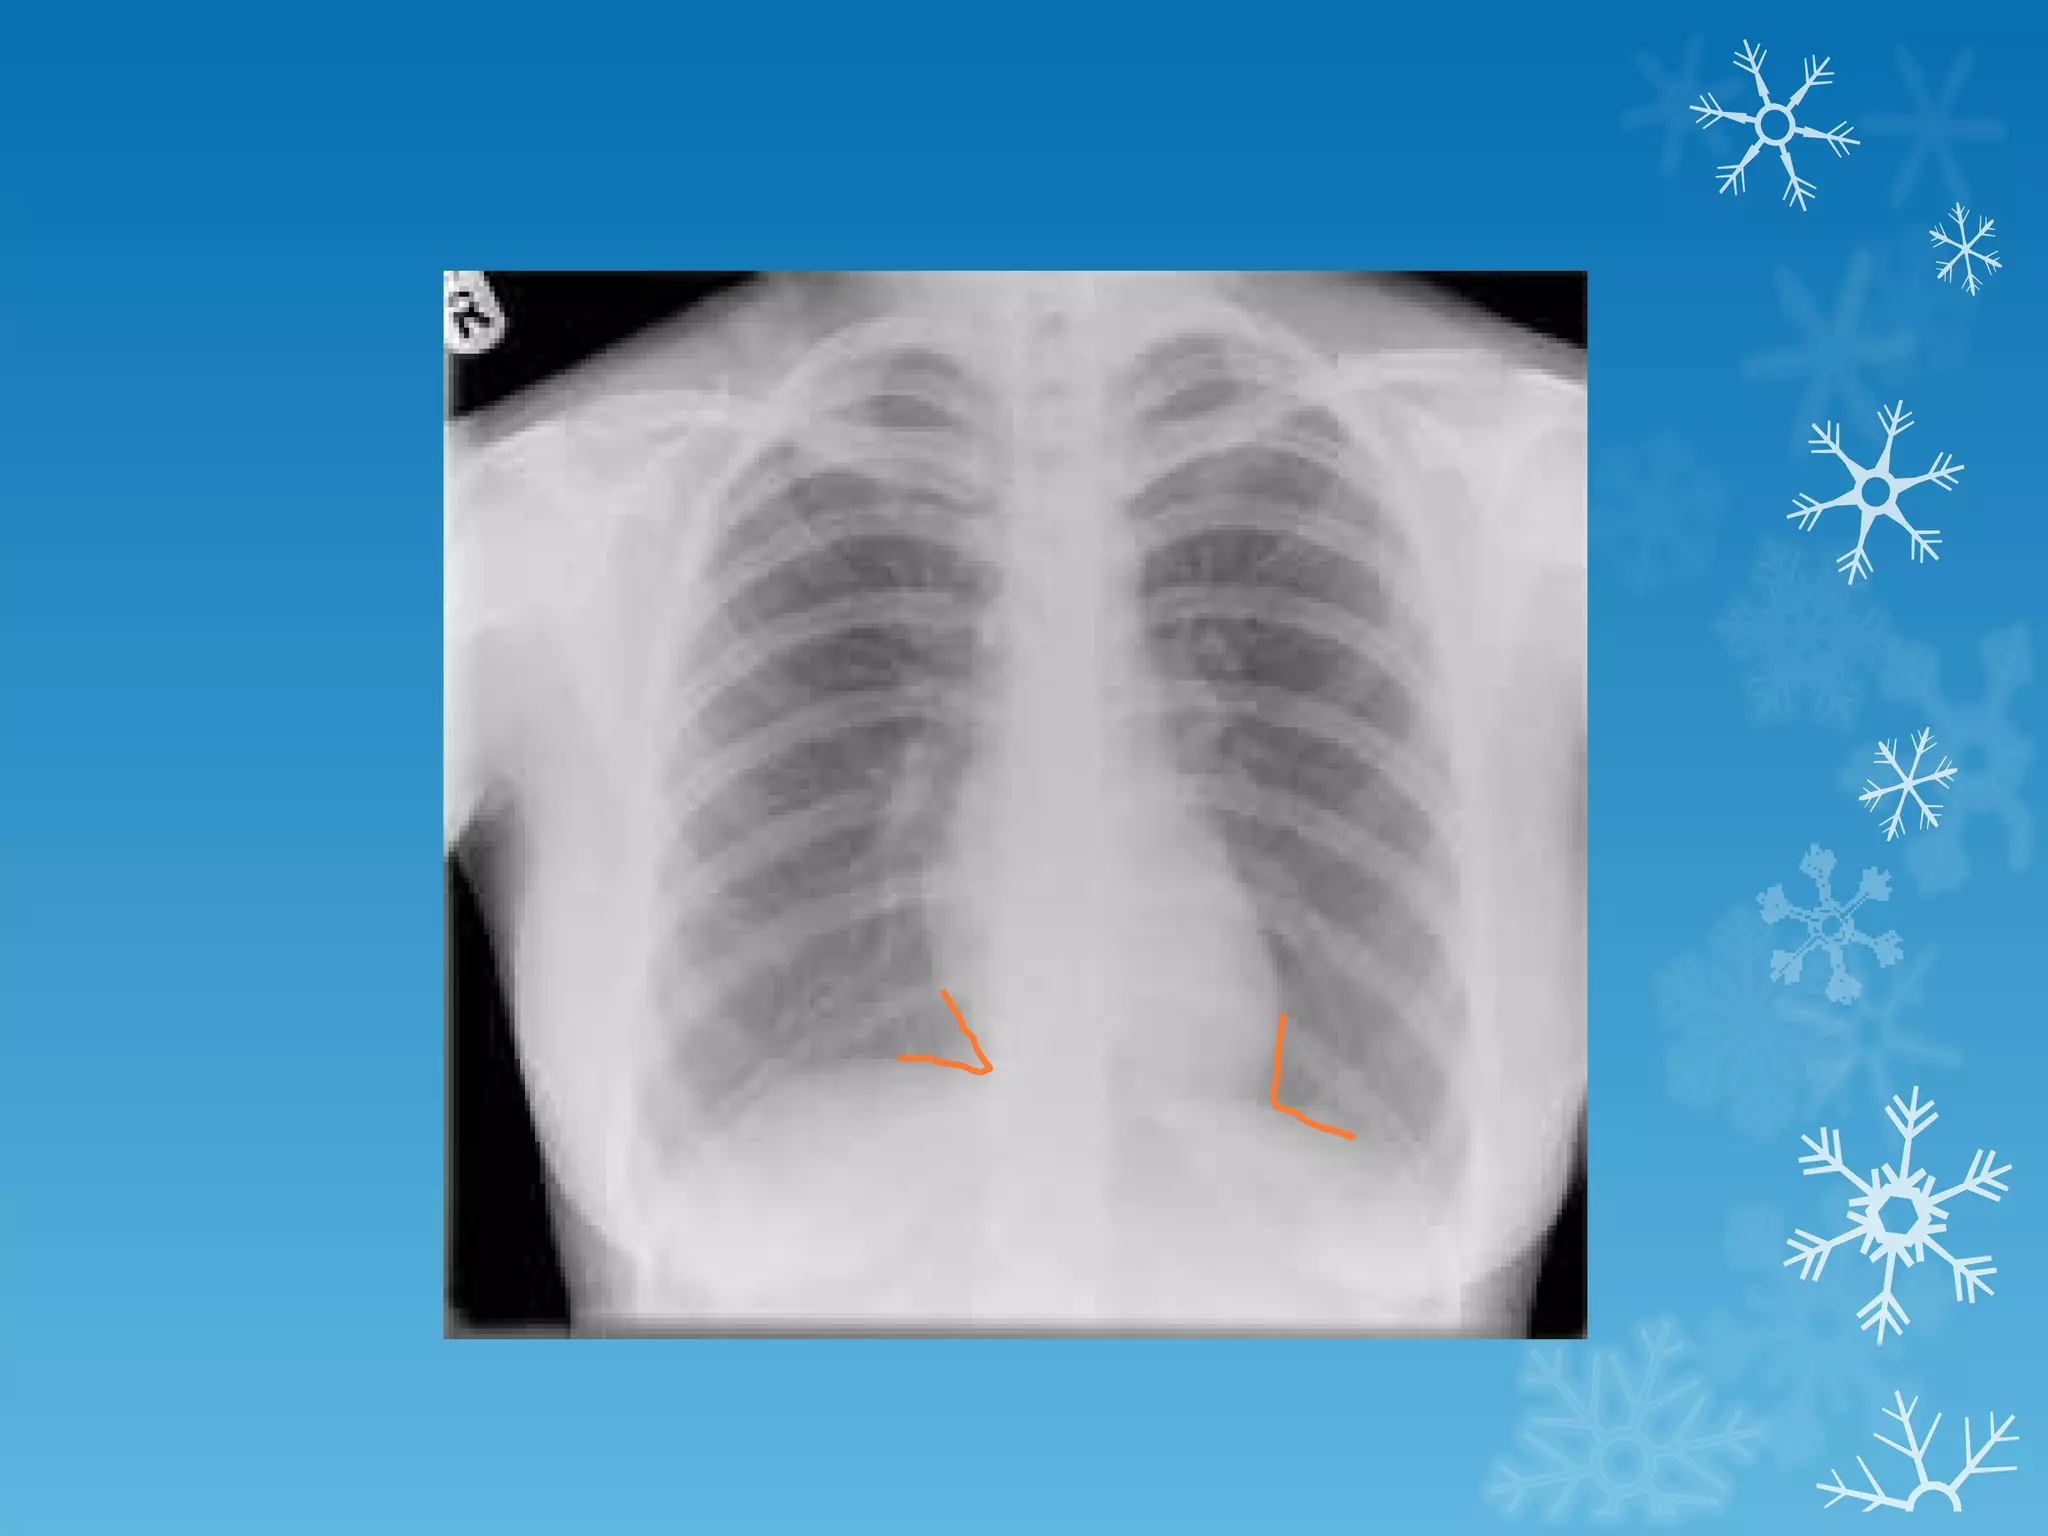

This document discusses chest x-ray interpretation and provides guidance on evaluating x-rays. It explains that tissue density determines how an x-ray beam penetrates, with denser tissues appearing whiter and less dense tissues appearing blacker. It also outlines different chest x-ray views and factors to consider like patient orientation, age, gender, and rotation. Abnormalities are described as appearing too white, too black, too large, or in the wrong place. The document stresses a systematic approach of identifying, localizing, describing lesions, and providing differential diagnoses.